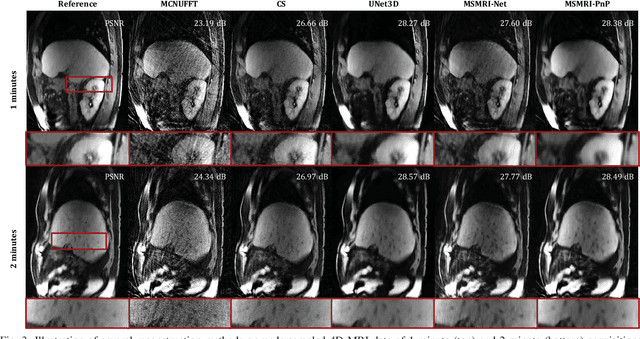

We propose a new plug-and-play priors (PnP) based MR image reconstruction method that systematically enforces data consistency while also exploiting deep-learning priors. Our prior is specified through a convolutional neural network (CNN) trained without any artifact-free ground truth to remove undersampling artifacts from MR images. The results on reconstructing free-breathing MRI data into ten respiratory phases show that the method can form high-quality 4D images from severely undersampled measurements corresponding to acquisitions of about 1 and 2 minutes in length. The results also highlight the competitive performance of the method compared to several popular alternatives, including the TGV regularization and traditional UNet3D.